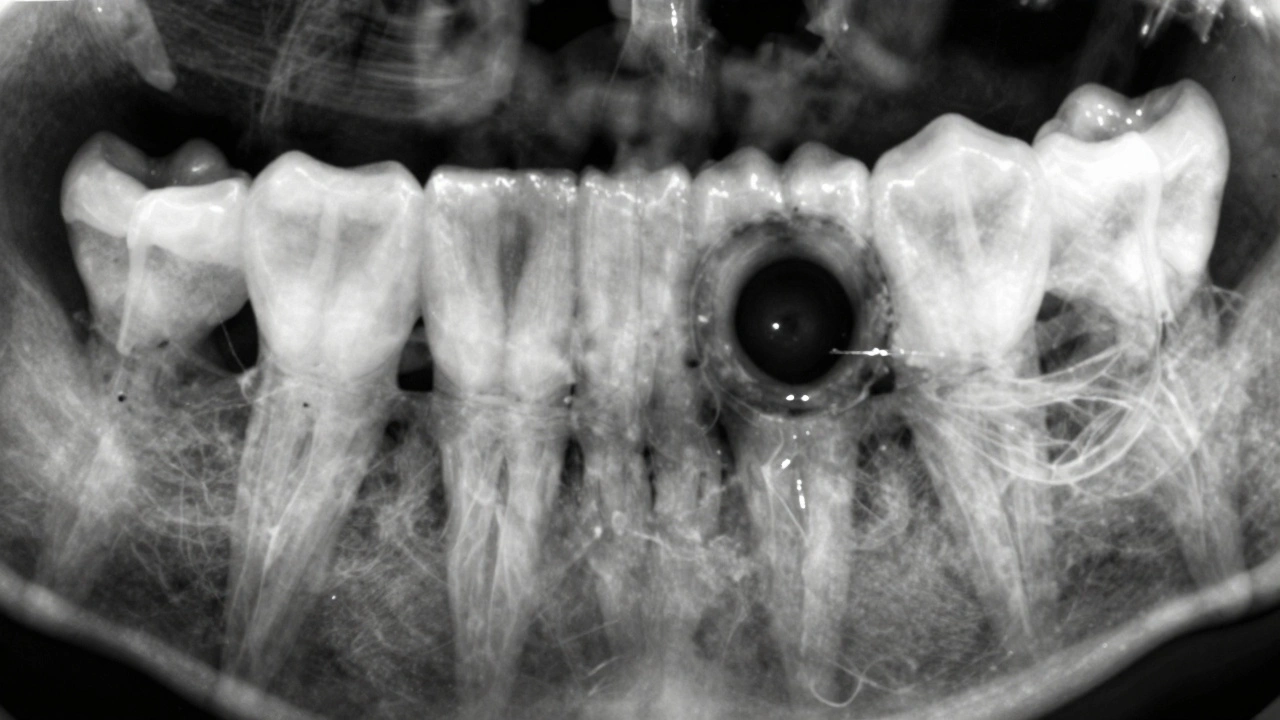

Co je jiného na rentgenu, když je kaz u kořene zubu

Když je kaz u kořene zubu, znamená to, že infekce se dostala až k místu, kde zub spojuje s čelistí. Na rentgenu to vypadá jako tmavý kruh kolem koncové části kořene. To je známka periodontálního abscesu nebo granulomu - tedy infekce v kosti. To není jen kaz, ale vážnější problém, který vyžaduje kořenovou léčbu nebo dokonce chirurgické zákroky.

Na rentgenu se také vidí, jestli je kost kolem kořene poškozená. Pokud je kost ztenčená nebo zcela zničená, znamená to, že zub už nemá dostatečnou podporu. A to znamená, že ho možná nebude možné zachránit. Dentista to vidí na rentgenu dříve, než začne zub být pohyblivý nebo bolet. A to je přesně ten okamžik, kdy se ještě dá něco udělat.

Rentgen kořene zubu s tmavým kroužkem na konci, označujícím infekci v kosti.